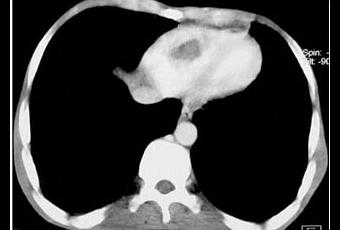

Angioscanner thoracique montrant une thrombose intra ventriculaire droite. In Revue des Maladies Respiratoires Volume 25, Issue 1, january 2008, Pages 69 - 72